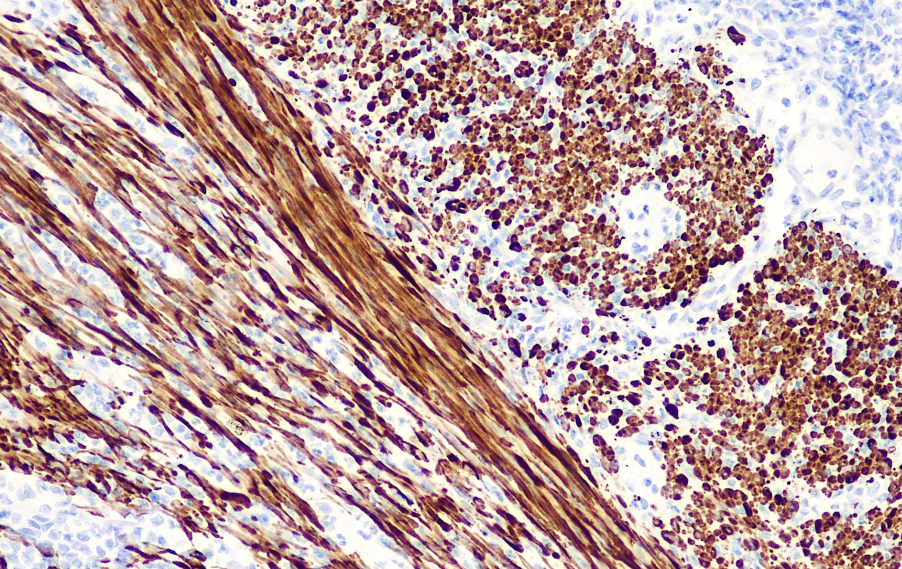

Smooth muscle myosin heavy chain is a polypeptide with a molecular weight of 200 kDa and is a structural component of hexameric myosin. It is primarily used for studying vascular and visceral smooth muscle cells as well as myoepithelial cells. It is considered a relatively specific and reliable reference for smooth muscle, aiding in the research and classification of mesenchymal tumors. It can also be used for detecting breast myoepithelial cells, facilitating studies on distinguishing between in situ carcinoma and invasive carcinoma.

Smooth Muscle Myosin Antibody Reagent specifically binds to the Smooth Muscle Myosin molecular antigen. The immunohistochemistry kit containing Smooth Muscle Myosin Antibody Reagent is suitable for the auxiliary diagnosis of mesenchymal tumors, carcinoma in situ, and invasive carcinoma.